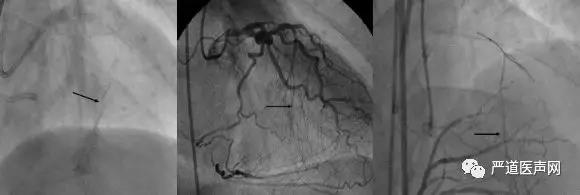

逆向侧枝可以分为CC0、CC1、CC2三级。CC0为供体动脉与受体动脉之间无明显连接;CC1为连续线性连接;CC2为峡部侧枝分叉尺寸较小。逆向侧枝通过应避免血管内迂曲成角、螺旋状、钙化等,其最佳类型为可以通过微型导管清晰显示CTO远端血管,包括CC1和CC2分级。

CC0级(左) CC1级(中) CC2级(右)